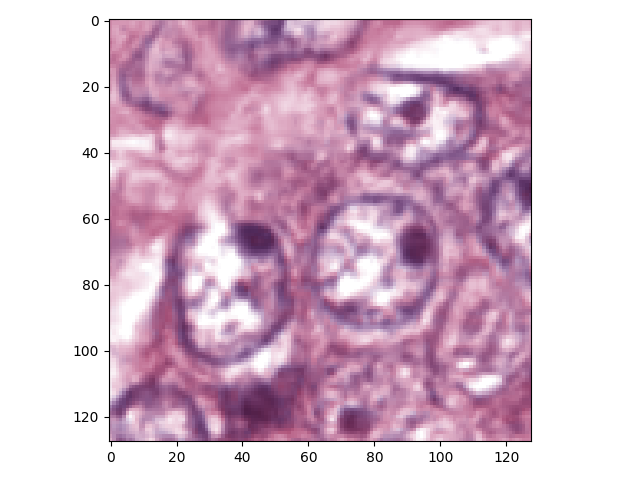

Our nuclei segmentation method adopts an end-to-end deep learning framework. The only preprocessing procedure is image color normalization. In the training phase, without extracting any features, even the H-channel, we directly apply the histopathology images in normalized RGB colors to the deep neural network to train the nucleus-boundary model. During the testing phase, the prediction result of raw normalized images yielded by the nucleus-boundary detector shows clear inside nuclei area and the boundaries. At last, we will obtain the area of each nucleus via a simple, fast and parameterless post-processing procedure. Fig.2 shows the procedure to segment nuclei from color normalized images in our algorithm.

H&E stain is the most widely used stain protocol in medical diagnosis. Typically, the nuclei of cells are stained to blue by Haematoxylin while cytoplasm is colored to pink by Eosin. But in practice, the color of H&E stained images could vary a lot due to variation in the H&E reagents, staining process, scanner and the specialist who performs the staining, as shown in Fig.1. A few H&E stain normalization methods[23, 24, 25] have been proposed to eliminate the negative interference caused by color variation. We tried two of them[23, 25] to normalize the raw H&E stained images. For our segmentation algorithm, we did not find any considerable difference between these two normalization methods. Particularly, the result shown in experiment section III is generated based on the images normalized by the method in [23]. Given a target image, this method is able to convert one image’s color into the target image’s color space based on sparse non-negative matrix factorization(NMF). We choose one best stained H&E image as the target and convert other images into its color space. According to the recommendation in [23], the hyper-parameter should be set between 0.01 and 0.1. In our experiment, is set to 0.1.

Intuitively, the pure Haematoxylin-channel grayscale image would be much easier than RGB images to distinguish the foreground (nuclei) from the background (cytoplasm). A large number of nuclei segmentation methods[26, 16, 27] employ some deconvolution algorithms to extract the H-channel from H&E stained images. However, based on our experiments, we noticed that our deep fully convolutional neural network extracts the nuclei from raw RGB images better than from H-channel grayscale images. The reason would be that the H-channel might miss some information that might be helpful for distinguishing nuclei and the cytoplasm. Given well-labelled training images, the deep neural network can then learn the optimal way to extract the features that discriminate between each category of samples. So we skip extracting H-channel and directly apply the RGB color image as the input to our deep neural network.